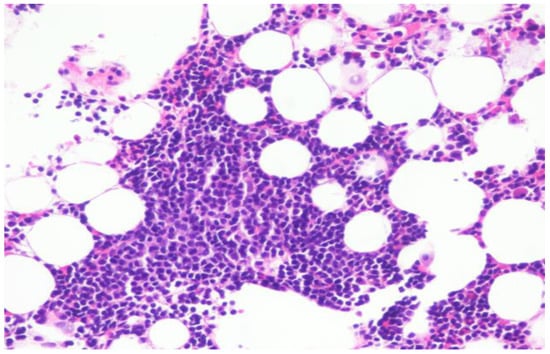

Ascitic fluid demonstrated increased lymphocytes (Figure 1) and flow cytometry was consistent with CLL (18% aberrant B lymphocytes) positive for CD5, CD19, CD20, CD23 [partial], CD45, lambda light chain [dim], and cytoplasmic Lambda [dim] and negative for CD2, CD3, CD4, CD7, CD8, CD10, CD11b, CD30, CD38, CD43, CD56, CD57, FMC-7, HLA-DR, kappa light chain, and cytoplasmic Kappa. Complete blood count revealed a WBC of 3.9 K, an absolute lymphocyte count of 1 K, and a platelet count of 102 K. Hemoglobin was 12.7 g/dL.

Figure 1. Peritoneal fluid with an increased lymphocyte population.